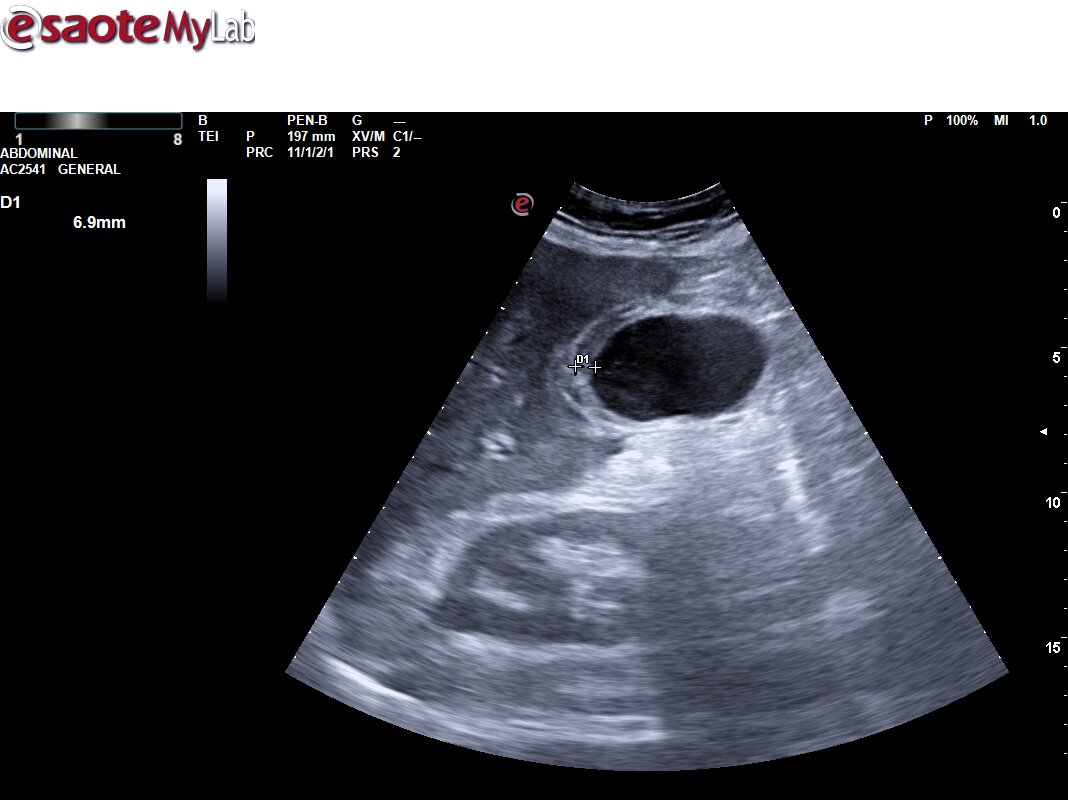

Ecografía Urgencias: Vesícula biliar de tamaño normal, con engrosamiento de la pared con edema de la mucosa. Pequeña colección perivesicular entre la pared vesicular y el reborde hepático de unos 10 mm de grosor, pérdida de continuidad de la pared vesicular compatible con pequeña perforación. Mínima lámina de líquido libre adyacente a la misma. Asocia también abundante contenido hiperecogénico en su interior en relación con barro biliar y varias litiasis en el infundíbulo vesicular. EcoMurphy +. Hallazgos sugestivos de colecistitis aguda complicada con colección / Abceso perivesicular. No líquido libre en los espacios abdominales explorados.